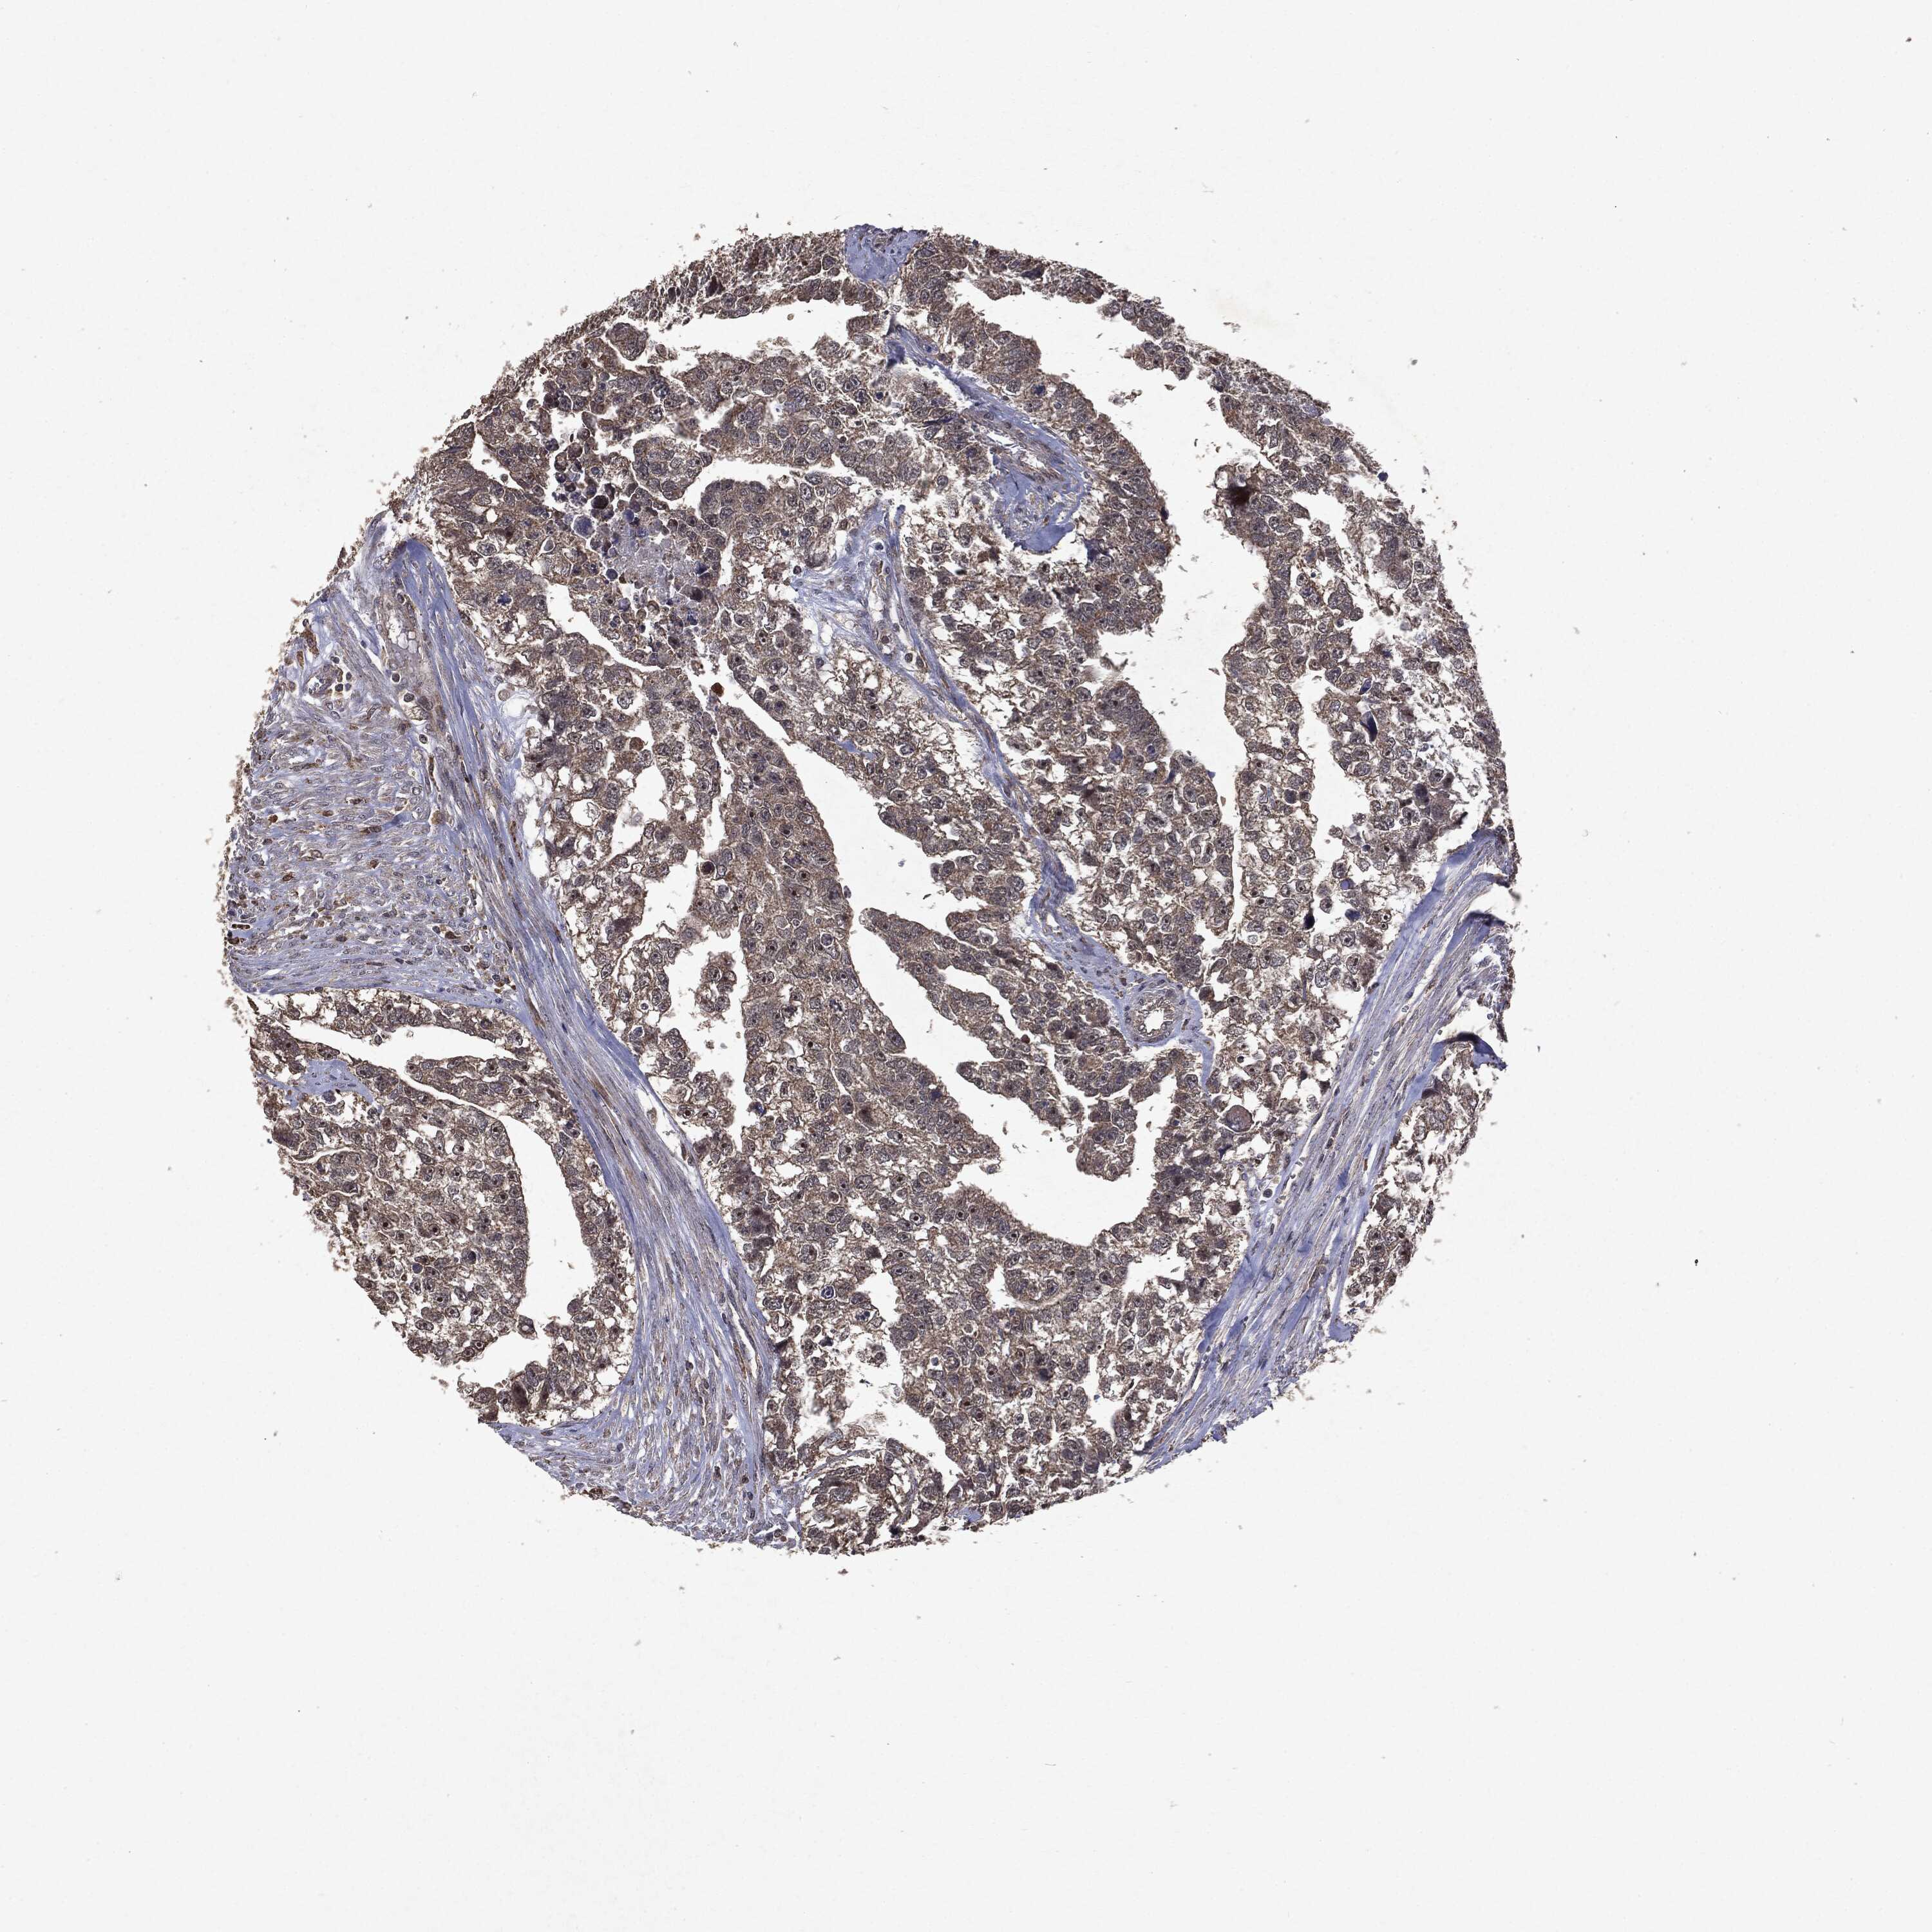

TESTIS CANCER - Protein expressioni

A mouse-over function shows sample information and annotation data. Click on an image to view it in a full screen mode. Samples can be filtered based on level of antibody staining by selecting one or several of the following categories: high, medium, low and not detected. The assay and annotation is described here.

Note that samples used for immunohistochemistry by the Human Protein Atlas do not correspond to samples in the TCGA dataset.

Antibody stainingi

Antibody staining in the annotated cell types in the current human tissue is reported as not detected, low, medium, or high, based on conventional immunohistochemistry profiling in selected tissues. This score is based on the combination of the staining intensity and fraction of stained cells.

Each image is clickable and will lead to virtual microscopy that enables deeper exploration of all samples and also displays staining intensity scores, fraction scores and subcellular localization as well as patient and tissue information for each sample.

Antibody HPA031335

Antibody CAB004076

Antibody CAB080153

Antibody CAB080157

Staining

High

Medium

Low

Not detected

Intensity

Strong

Moderate

Weak

Negative

Quantity

>75%

75%-25%

<25%

None

Location

Nuclear

Cytoplasmic/membranous

Cytoplasmic/membranous,nuclear

Seminoma, NOS

Carcinoma, Embryonal, NOS

Teratoma, malignant, NOS

Urothelial carcinoma, High grade